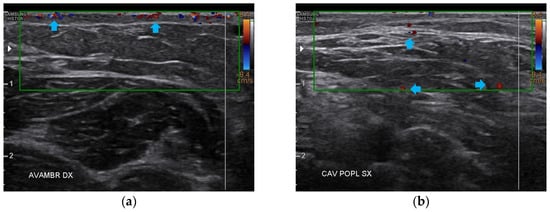

3.1. Basal Imaging Evaluations

3.2. Imaging Evaluations After the Treatment